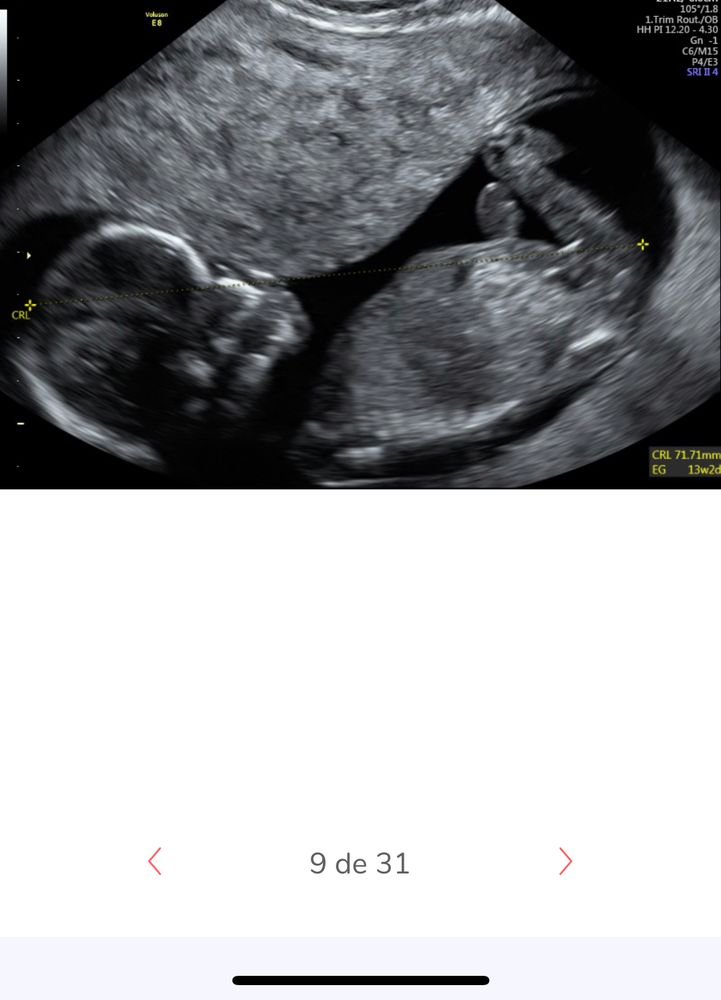

Половой бугорок? Пол?

Пол малышаДевочки, мне кажется или это действительно половой бугорок?

я сейчас о горизонтальной белой полосочке справа?

или мне кажется и на 13 неделе ещё толком ничего не ясно

но вот на этом фото мне кажется то но бугорок ( слева обе ножки)